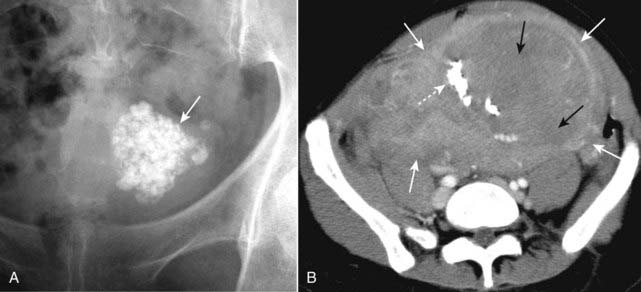

image

Figure 16-12 Calcified uterine leiomyoma (fibroid) on conventional radiograph (A) and CT (B).

A, There is an amorphous (or popcorn, if you’re hungry) calcification (solid white arrow) visible in the pelvis of this 48-year-old female. The type of calcification suggests formation in a solid organ or tumor. This is the anatomic location and the classical appearance of calcified uterine leiomyomas (fibroids). B, Another patient has large uterine fibroids (solid white arrows), portions of which have necrosed (solid black arrows) and calcified (dotted white arrow). Ultrasound is the study of choice in diagnosing uterine fibroids.